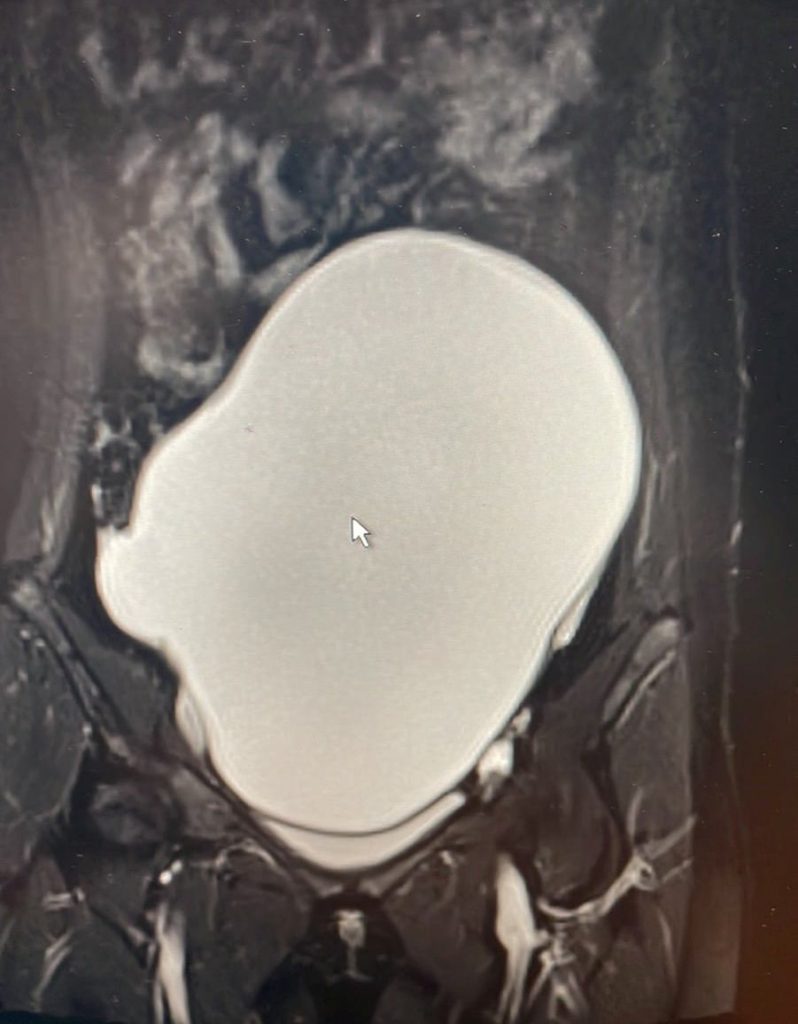

Львівські лікарі видалили із яєчників 14-річної дівчини 3-кілограмову пухлину. У пацієнтки був збільшений живіт, який їй заважав.

“Дівчинка з 9 років хворіє на лейкемію. Вона отримувала все необхідне лікування — і променеву, і хіміотерапію. В Італії їй зробили пересадку кісткового мозку. Зараз вона у ремісії. У процесі лікування пацієнтка мала також гормональну терапію, ймовірно, це і стимулювало ріст пухлини у яєчнику. Батьки дівчинки зверталися в різні клініки до різних спеціалістів вже з новою проблемою, їм рекомендували стежити за «кістою», проте в якийсь момент утворення досягло просто гігантських розмірів”, — розповідають у лікарні.

Симптомів у дівчинки не було — лише значно збільшився живіт, який суттєво заважав.

В операційній лікарі отримали близько 3 літрів рідини і масивну капсулу пухлини.

“Ситуація була непростою, адже гігантське утворення в яєчнику було бомбою і вже навіть не сповільненої дії. Компресія навколишніх органів і ймовірність злоякісної трансформації самої пухлини вимагали швидкого реагування! Усе заплановане в операційній нам вдалося. Попереду у дівчинки ще тривалий процес реабілітації репродуктивної функції”, — каже дитячий гінеколог Еліна Чайківська.